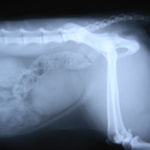

症例:交通事故による椎体脱臼

柴犬:9歳、避妊雌

交通事故直後、胸腰部に激しい疼痛、両後肢に完全麻痺を認め、シェフシェリントン徴候を呈していました。レントゲン検査において、第11-12胸椎間の脱臼が認められました。

脊髄の減圧、脊柱管の再構築・安定化を目的に、片側椎弓切除術およびMatrixMANDIBLE Plateによる椎体固定を実施しました。

隣接椎体を架橋するようにプレートを設置しました。

術後レントゲン写真